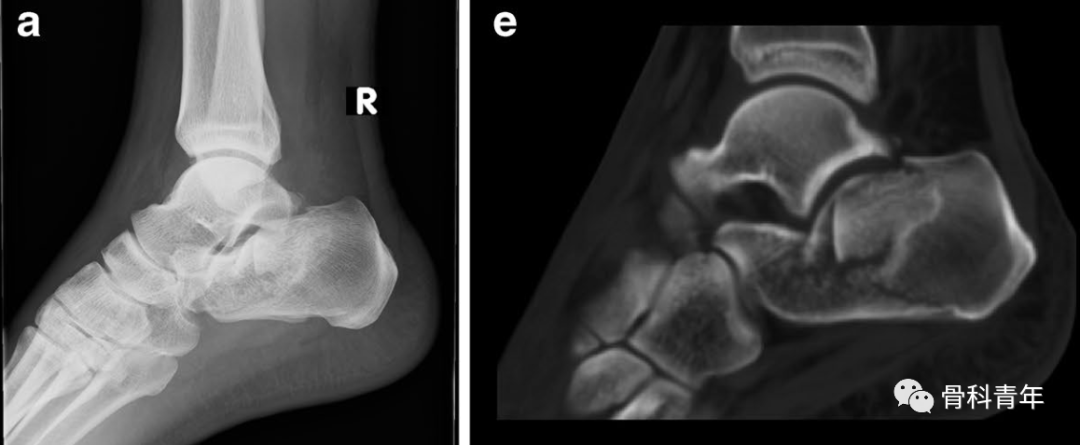

2.经后结节跟腱内下方止点处,沿与胫骨呈45°方向,置入一枚2mm克氏针,可见跟骨宽度增宽。